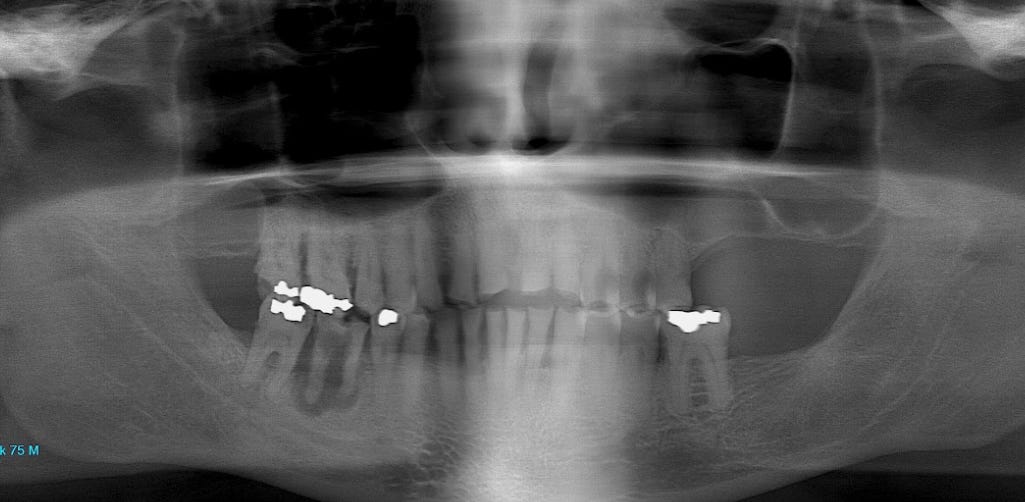

Frank has a tooth in his lower right jaw that has been hurting him for years. (This is your left as you look at the x-ray.) He recently started Frontier Pharm’s chlorine dioxide (CD) mouthwash*, and the pain disappeared on the first day. His recent x-ray shows five mercury amalgams and a huge abscess around the painful tooth. This shows up as a clear area around a root in the lower jaw to your left: